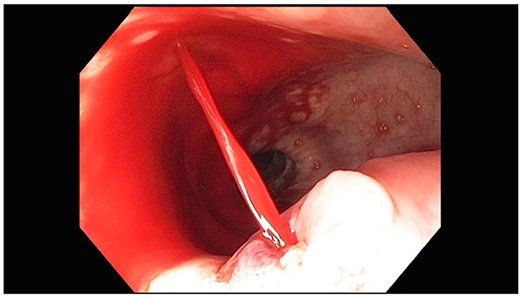

A 71-year-old male with past medical history of type 2 diabetes and hypertension presented to the emergency department at St. Joseph’s University Medical Center with severe respiratory distress. On nonrebreather, the patient’s oxygen saturation was 49%. The patient was subsequently intubated. Evaluation revealed pneumonia secondary to COVID-19 leading patient to be intubated on ventilator support for 4 weeks. During this time patient was maintained on enteral feeding through nasogastric tube, and was on gastrointestinal prophylaxis Protonix 40 mg daily for the duration of his admission. Ultimately, the patient made full recovery and was sent home; however, approximately 3 weeks later, he presented to the emergency department due to syncope. The patient experienced large-volume bright red hematemesis. He became hypotensive and was transfused three units of packed red blood cells and started on pressors. The patient was intubated and transferred to the intensive care unit (ICU) with acute blood loss anemia and hypovolemic shock. Here, an esophagogastroduodenoscopy (EGD) was performed revealing midesophageal bleed (Fig. 1). Hemostasis was achieved with clipping; however, post-procedurally, the patient again became hypotensive. Repeat EGD showed a nonbleeding esophageal ulcer with three clips in good position (Fig. 2). Computed tomography (CT) angiogram of the thorax was performed revealing an actively bleeding aberrant right subclavian artery perforating into the esophagus (Figs 3 and 4). The right subclavian artery was noted to be of normal caliber without ectasia or aneurism and the esophagus was free of any other pathology. Thoracic and vascular surgery were consulted; however, the bleed was deemed of nonsurvivable pathology due to comorbidities and current clinical status. Ultimately, the family of the patient decided to withdraw care and the patient passed.

CT thoracic showing the arch of the aorta with the take-off of the right subclavian artery (red arrow) distal to the left subclavian artery.